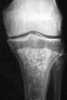

Osteonecrosis of the intercondylar spines of the tibia

Caffey tibial spine osteonecrosis